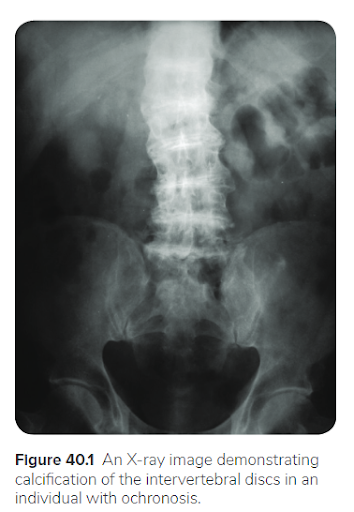

24 Qs1. A 50-year-old man comes to the clinic for evaluation of chronic back pain. He works as a librarian and notes that the pain is localized to his lower back and worsens after a long day of standing. The pain has not improved despite treatment with ibuprofen. Past medical history is significant for osteoarthritis of his right hip, for which he underwent a total hip replacement 2 years ago. Family history is noncontributory. Temperature is 37.0°C (98.6°F), pulse is 86/min, respirations are 16/min, and blood pressure is 125/85 mmHg. Ophthalmic examination reveals a bluish pigment deposition in the sclera. Dermatological examination reveals hyperpigmentation in the axillary and inguinal regions. Range of motion at the spine is limited. An x-ray of the erect spine is shown below:

Laboratory evaluation reveals elevated levels of homogentisic acid. The production of which of the following end products is likely to be inhibited, considering the most likely diagnosis?